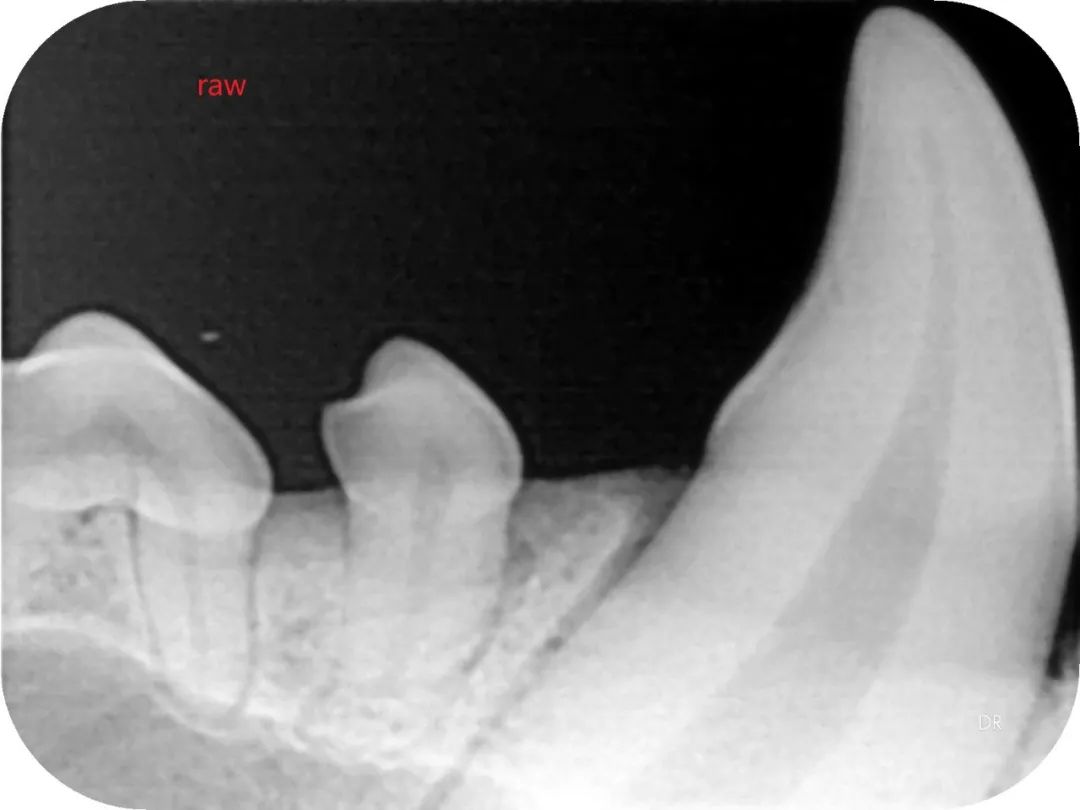

▲院内新进牙科DR设备之一

▲部分牙科DR效果展示图(可左右滑动)

什么是DR?

DR检查是影像科常用的一种检查方法,它又称为数字化X射线摄影系统,相对于传统的拍片子检查,它的辐射量更小,检查的时间更短,片子的质量也更高